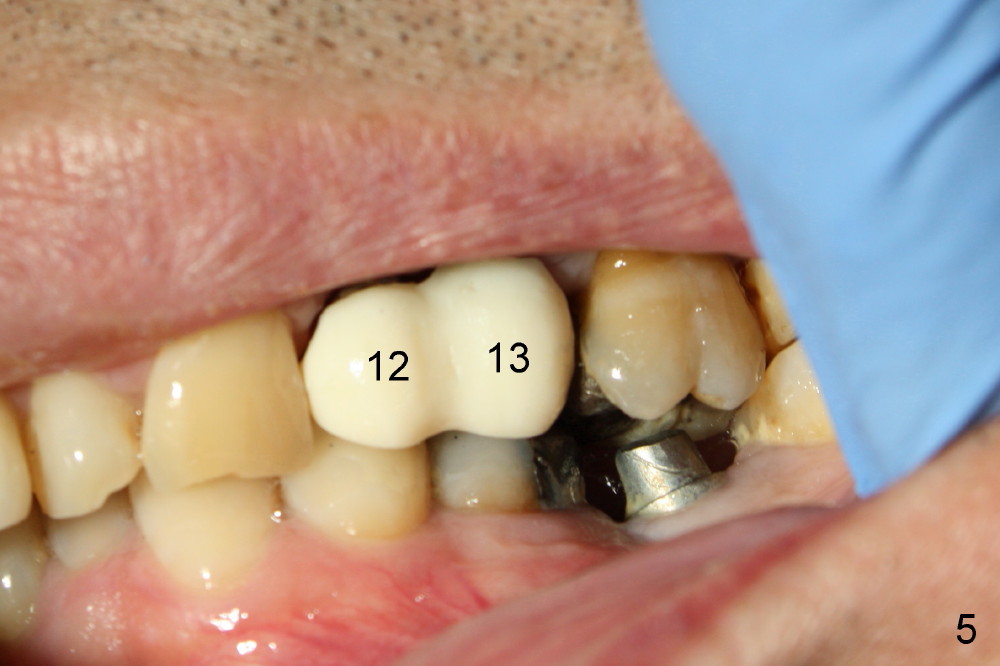

A 51-year-old man needs implants at the sites of #12,13,19 (Fig.1). The teeth #12 and 13 are extracted. An implant is placed at #19 (Fig.2 <). After osteointegration, an abutment is placed (Fig.2 A). The opposing tooth, #14, is found supraerupted. Two mini-implants are placed at the mesiobuccal and distolingual areas of #14 (Fig.3 (mirror view) <) and a power chain (*) is placed for intrusion. In the next 8 months, these 2 mini-implants become loose. Two new mini-implants are placed in the mesiolingual and distobuccal regions (Fig.4 ^). The one in the distobuccal region is loose after a while (Fig.6,7 >). In brief, mini-implants are not efficient in intrusion. At this time, the implants at the sites of #12,13 apparently osteointegrate (3 months post placement) and abutments are placed (Fig.4). Provisional crowns are fabricated (Fig.5). Brackets are placed between #11 and 15 with the bracket at #14 placed more coronally than those of the neighboring teeth (Fig.6-8). Mesially there are two excellent anchorages (#12,13) as well as the mesiolingual mini-implant. The distal anchorage is #15. In the next 5.5 months, the tooth #14 is intruded (Fig.9,10), but the 2nd molar is mobile (not as strong as #14). A longer mini-implant is placed in the distobuccal corner (>, more apical than before (Fig.7)). The distobuccal mini-implant is found to be mobile in 3 weeks (Fig.11). It appears that there is enough clearance for restoration of #19 (Fig.12). Power chains are placed between the mesiolingual mini-implant and #14 buccal tube until the appointment for crown prep. In this way, the lingual cusps may ascend (Fig.13 red arrow), while the buccal ones may descend (black arrow). The occlusal clearance will be more favorable.